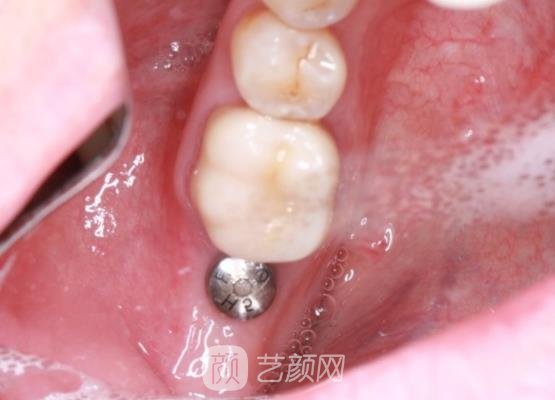

之后就开始进行牙齿种植,在牙齿种植的过程中,医生的技术手法也很娴熟,然后就将种植体植入到了没有牙齿的部位,现在有一颗种植体存在我的口腔里面,虽然比较影响美观,但是后续还会在上面安装假牙,那样就能够遮盖住。

这几天由于刚刚植入了种植体,所以现在局部已经出现了肿胀和疼痛的现象,为了让局部恢复的更好一些,我这几天吃东西都不敢用,这边的牙齿去咀嚼,已经换另一边健康的牙齿咀嚼食物,而且吃的也很软烂,每天都很注意口腔的清洁卫生。

现在已经过去了三个多月的时间了,我再次前往医院,医生又为我做了一系列的检查,种植体已经与我的牙槽骨相融合了,之后医生讲其他的材料都安装在了上面,现在种植牙才变得很真实自然了。